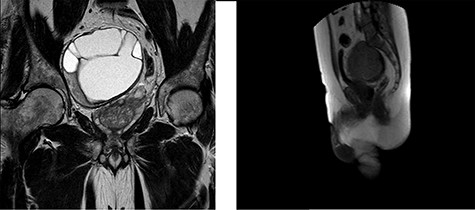

A 62-year-old male presented to our department with a history of abdominal heaviness and dysesthesia in the lower limbs for ~6 months. A computed tomography scan showing an expansive mass needing further investigation through MRI. MRI highlighted, in the pelvic excavation, a paramedian, well-defined heterogeneous lesion of mixed-signal intensity of ~115 × 105 × 92 mm with polylobulate margins and multiple intralesional septa (Fig. 1), which is characterized by heterogeneous hyper-intensity of signal in the T2-weighted sequences and hypo-intensity in T1. An ultrasound-guided biopsy was suggestive for schwannoma.

MRI of the pelvis in the Coronal Plane (left) and Sagittal Plane (right) demonstrating a 115 × 105 × 92-mm sacral schwannoma, displacing the prostate and rectum to the left side.